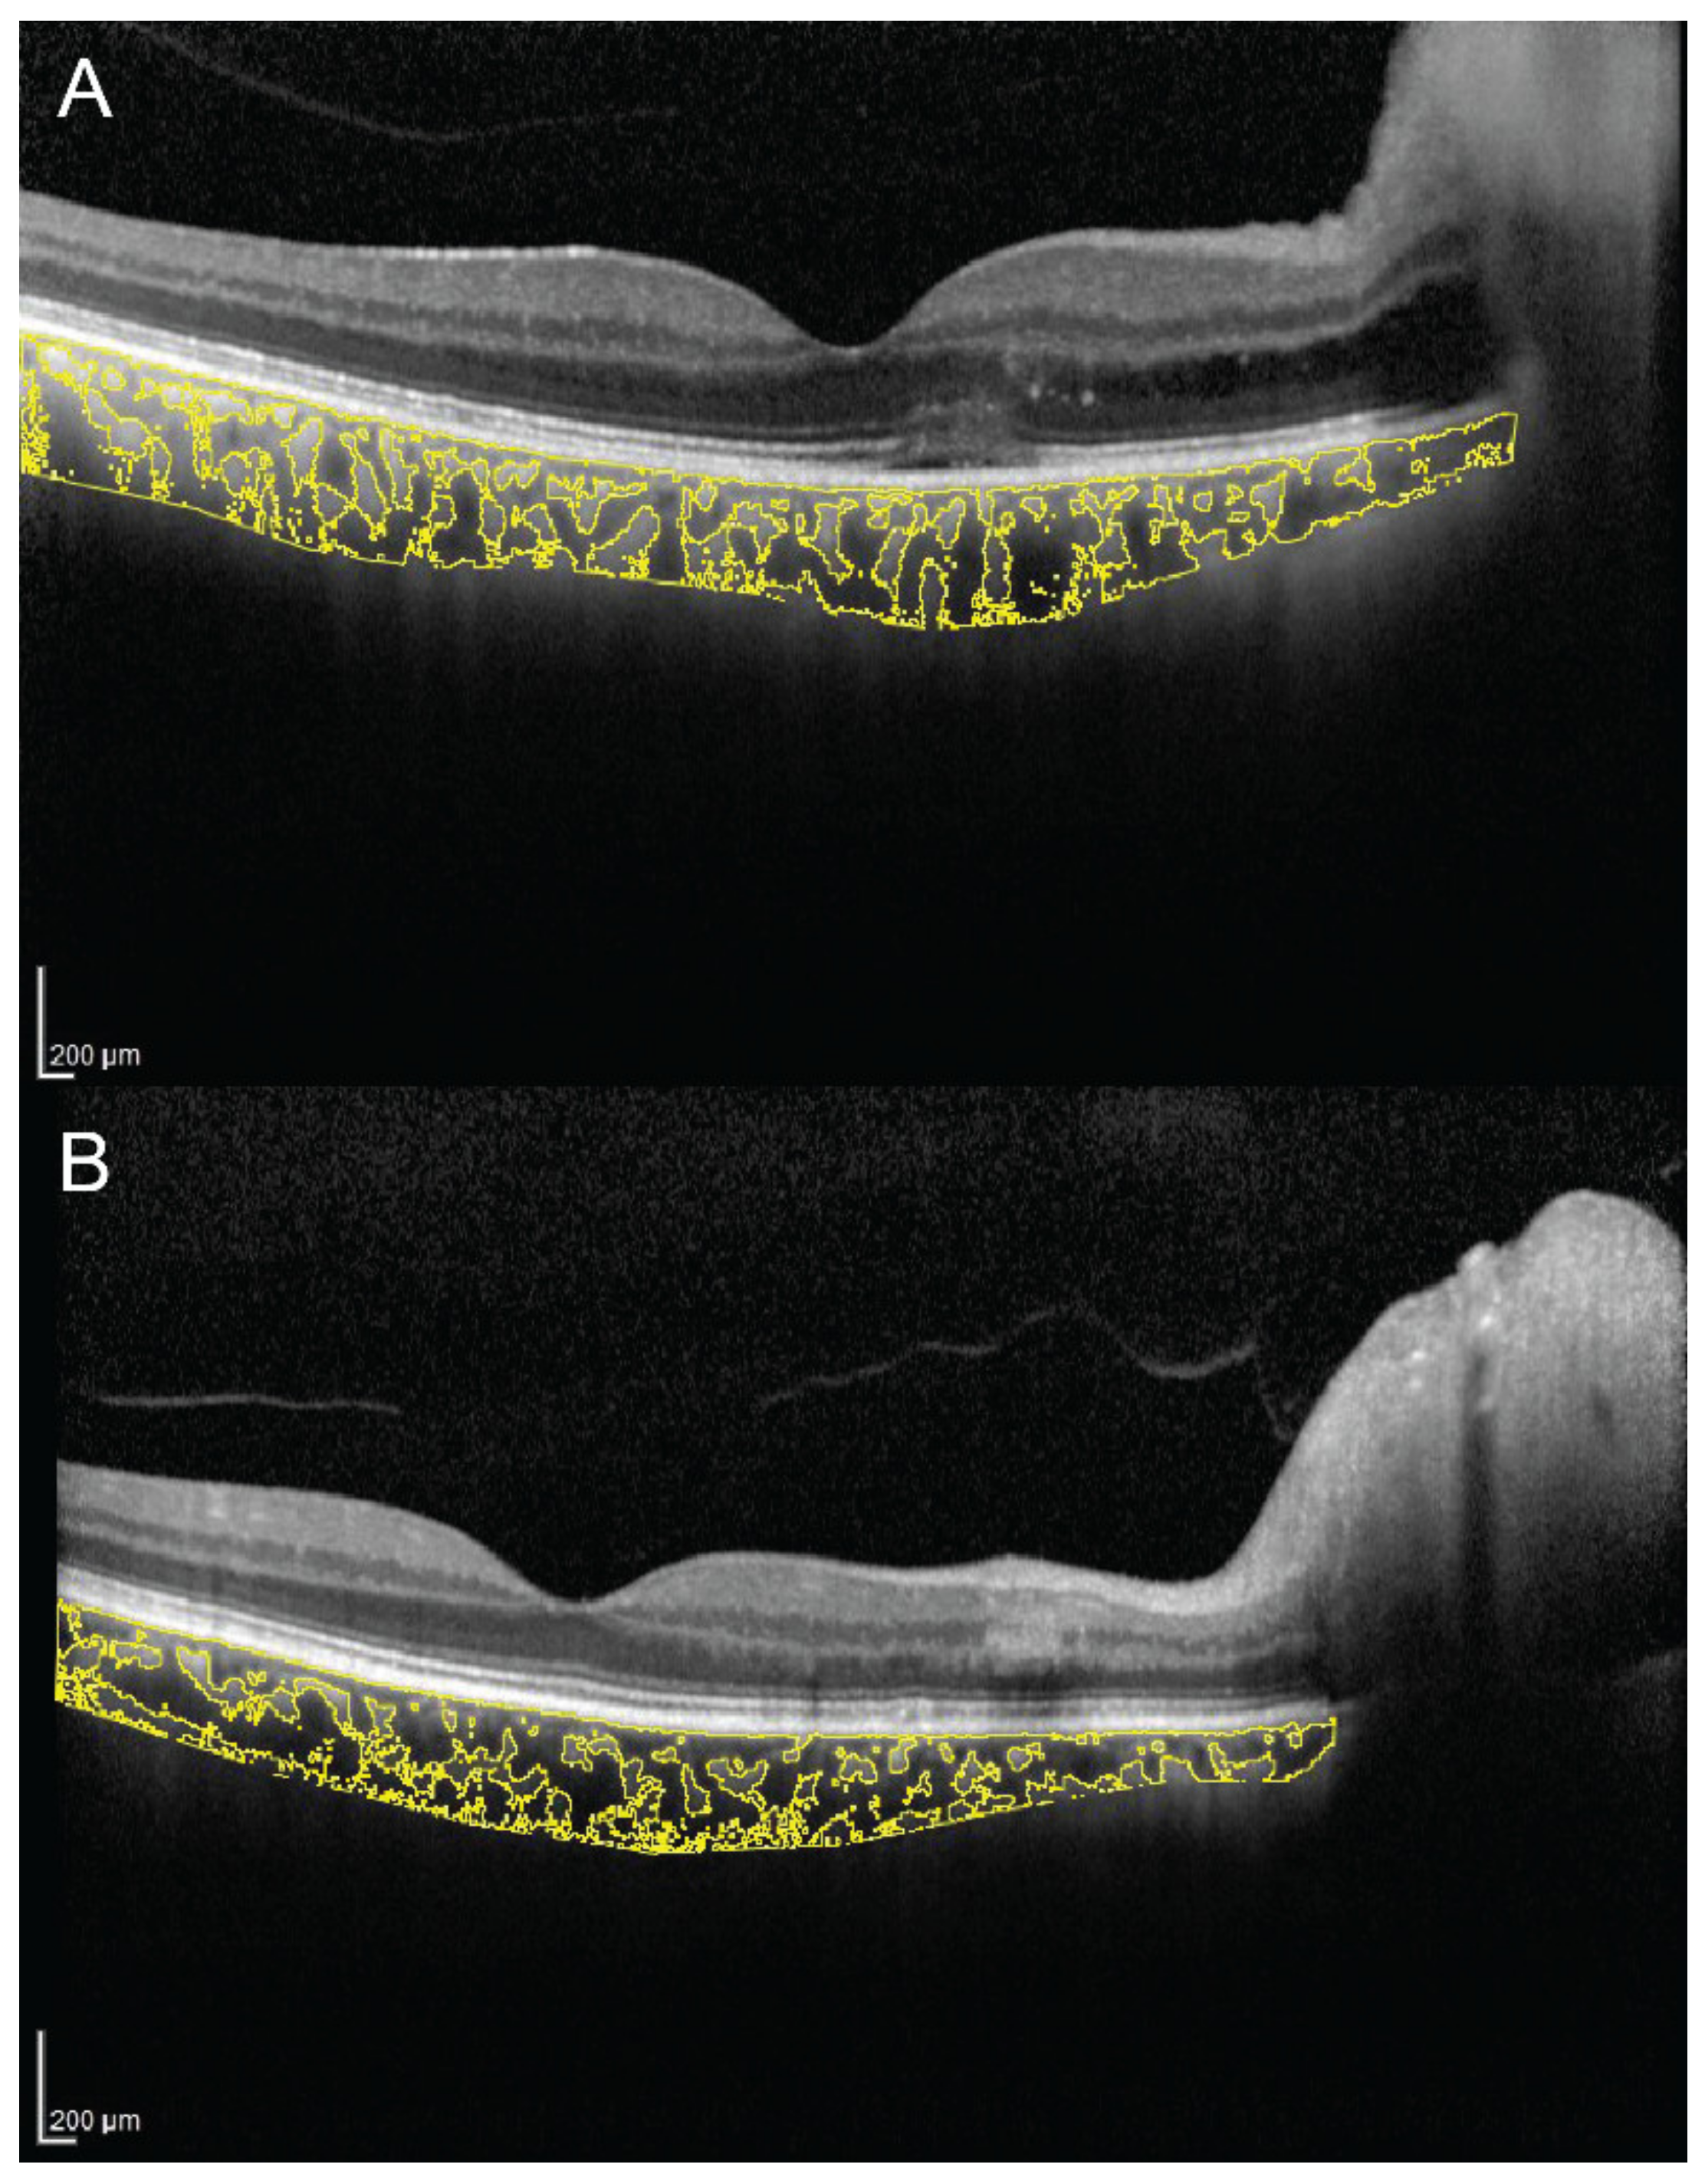

Additionally, CVI was evaluated to compare the effect of full-dose, half-dose (full fluence) and half-dose half-fluence photodynamic therapy (PDT) in CSC [47]. At 3-month follow-up in full-dose and half-dose (full fluence) group, CVI decreased and visual acuity improved significantly. The evaluation of CVI in a representative case of a 56-year-old man with chronic CSC, before and 3 months after half-dose full-fluence PDT, is shown in Figure 3. Conversely, in the half-dose half-fluence group it was significantly increased but no significant visual acuity improvement was recorded. The reduction of subfoveal CT after PDT was statistically significant in all three groups. The results of this study suggest that the effect of PDT on the half-dose half-fluence group was less clear than in the other groups [47].

Figure 3. Choroidal vascularity index, calculated by the means of automated algorithm in a 56-year-old man with chronic central serous chorioretinopathy (CSC), before (A,B) and 3 months after (C,D) half-dose full-fluence photodynamic therapy, was 58.7% and 54.4%, respectively.

The authors wish to thank J. Chhablani for providing Figure 3 where the CVI was assessed through an automated algorithm.